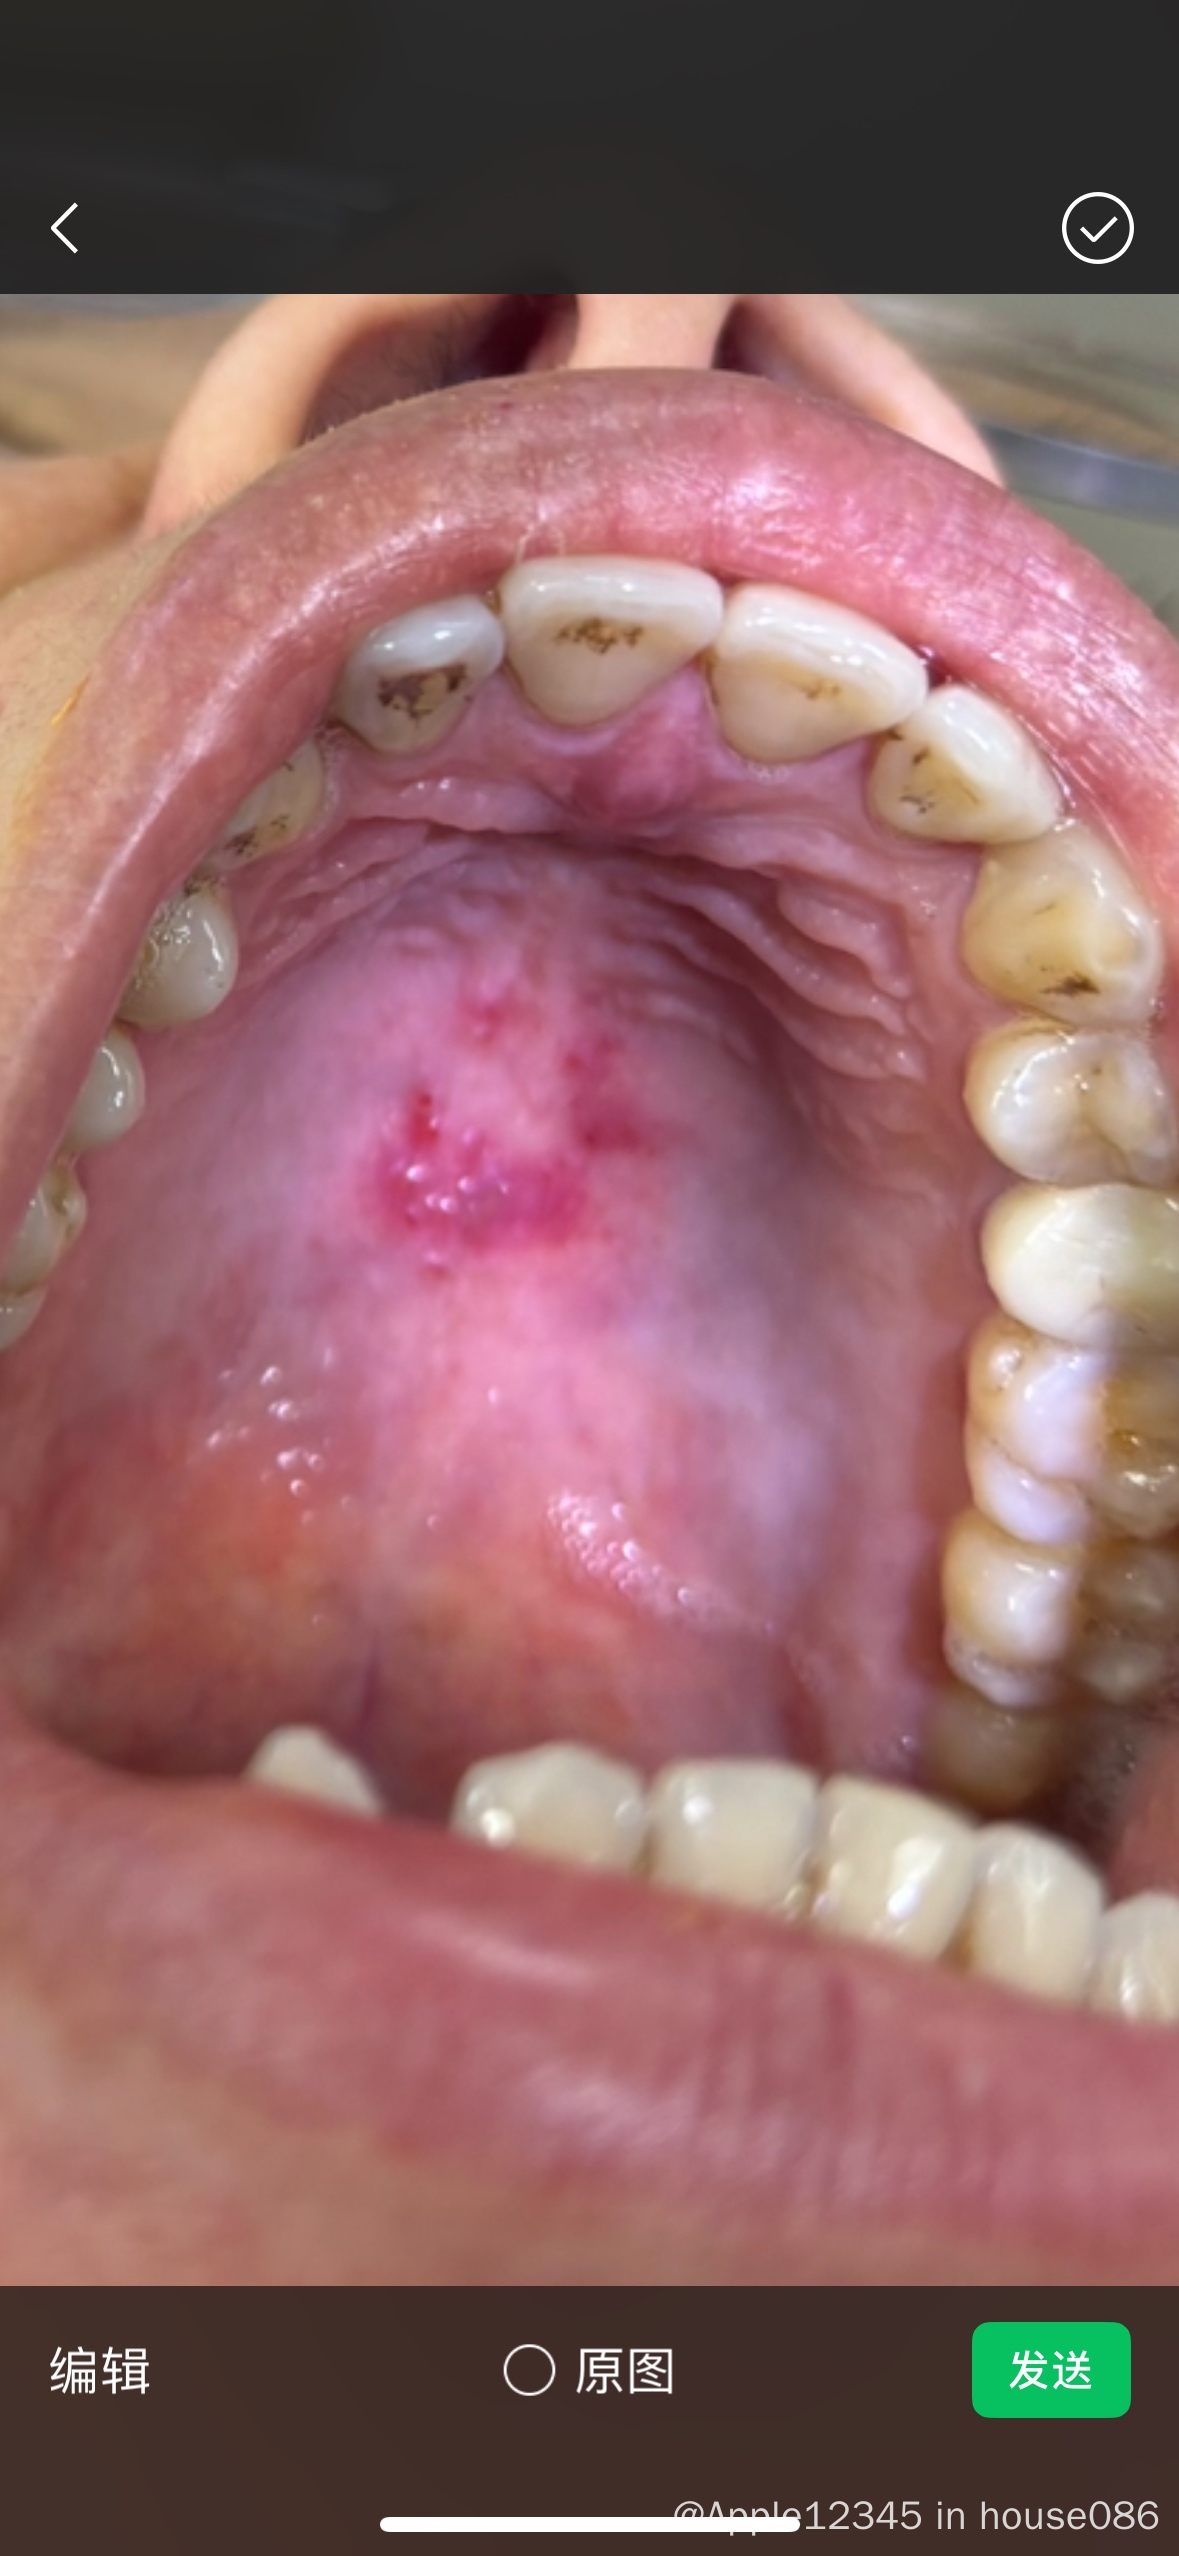

上颚红肿斑块

上颚出现在这个,有可能是nkt吗?

这看起来像口腔上火后吃了硬物打出来的